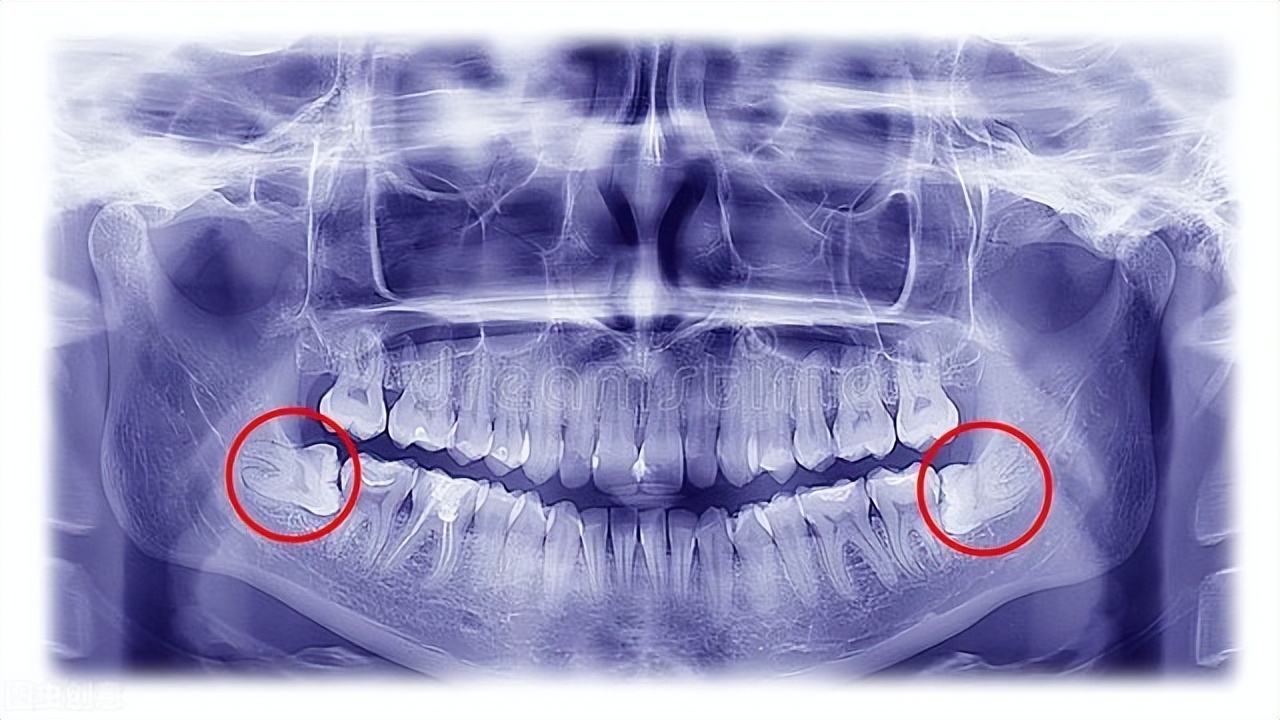

4、反复发炎的智齿

反复发炎的智齿,容易影响日常生活,还易造成其他邻牙受累,并且智齿拔除后,对于正常的咬合不存在太大影响。因此对于反复发炎折磨你的智齿,拔除会更好。